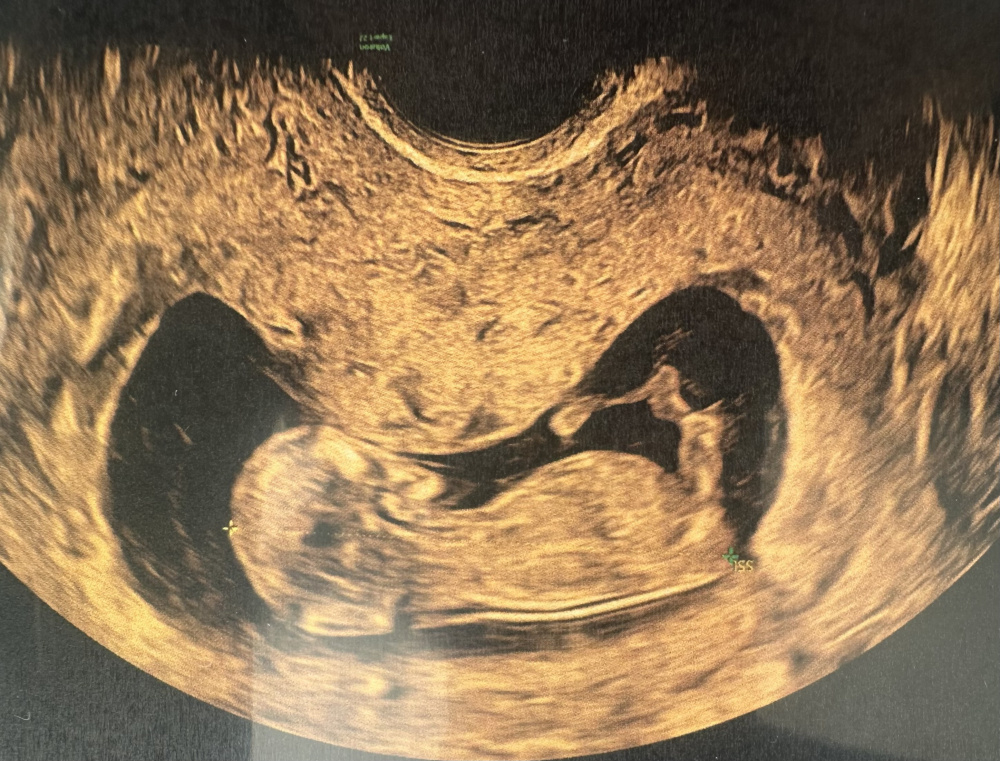

Guten Morgen,

ich bin derzeit in der 13. SSW und hatte letzte Woche einen Ultraschall. Was meint ihr, kann man das Geschlecht erkennen? Der Arzt hatte eine klare Tendenz die er uns leider bisher nicht mitgeteilt hat. Ich kann leider nichts wirklich erkennen. Hier die Bilder aus 12+3. Vielen Dank fürs Miträtseln.

@Memyslefandi Vielen Dank, dass du dir die Zeit genommen hast. Woran hast du es erkannt? Beim ersten Bild steht so viel ab, ich dachte sofort an einen Junge. Mein Mann wünscht sich so sehr einen Sohn

Ein Mädchen 🥰